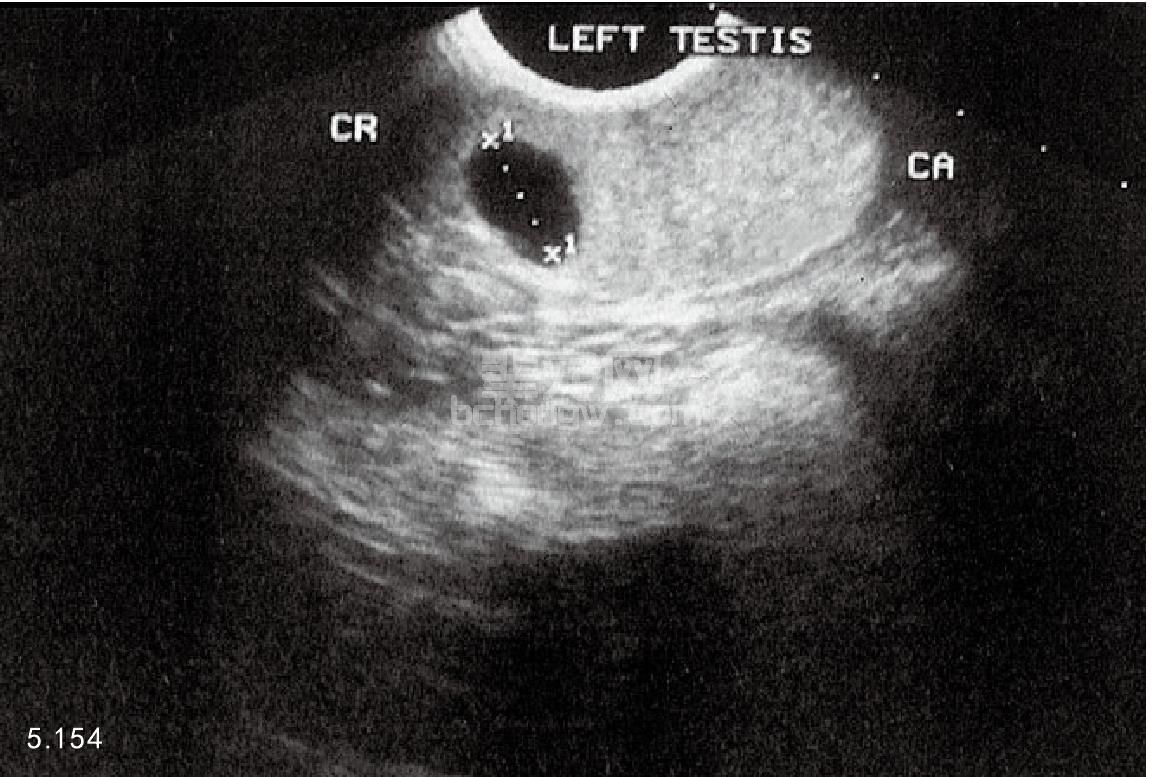

骨盆和腹腔的X线照相和超声波检查 超声波检查可以提供有关睾丸(图5.154)和附睾损伤与否及肿瘤、睾丸不下、睾丸扭转、腹股沟疝和前列腺的疾病(图5.155和图5.156)。超声波检查还可以用于前列腺穿刺针活组织检查和抽吸的监视。X线片有助于诊断腹腔后部的前列腺疾病。

图5.154 超声检查犬的睾丸,在睾丸头部(CR)邻近附睾的位置出现空洞损伤。该病灶是塞尔托利(Sertoli)细胞肿瘤,可以做单侧睾丸切除术。